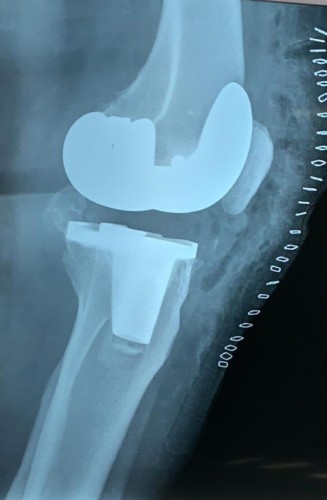

نجح فريق متخصص في مستشفى محافظة وادي الدواسر العام، من إجراء جراحة ناجحة تمثلت في استبدال مفصل ركبة بمفصل صناعي لمريضة سبعينية كانت تعاني من آلام بالركبة وعدم القدرة على المشي مع توقف لمعظم الأنشطة الحياتية.

وفي التفاصيل، قرر فريق العظام بمستشفى وادي الدواسر، بقيادة استشاري جراحة أوارم العظام والجراحة الترميمية للأطراف السفلية وجراحة تغيير مفاصل الركبة والورك الطبيب الزائر إبراهيم الشايجي، من إجراء عملية دقيقة لأحدى المرضى المترددين على عيادة المفاصل بالمستشفى، وذلك بعد تشخيص حالتها بخشونة متقدمة في مفصل الركبة اليمنى مع معاناة شديدة من آلام بالركبة وعدم القدرة على المشي، مما أدى إلى توقف لمعظم الأنشطة الحياتية.

وأكد الطبيب “الشايجي”، أنه وبتوفيق من الله- تمكن الفريق الطبي من إجراء العملية بنجاح وهي استئصال مفصل ركبة واستبداله بمفصل صناعي؛ وقد بدأت المريضة برنامجها بالحركة والمشي؛ لتكون ثاني حالة من حالات تغيير مفاصل الركبة في مستشفى وادي الدواسر العام، بدعم من مدير عام الشؤون الصحية بمنطقة الرياض الدكتور حسن بن علي الشهراني ، ومتابعة المساعد للخدمات العلاجية الدكتور علي بن سليمان الجمعة ، وكذلك إدارة المراكز المتخصصة والطبيب الزائر بصحة الرياض.